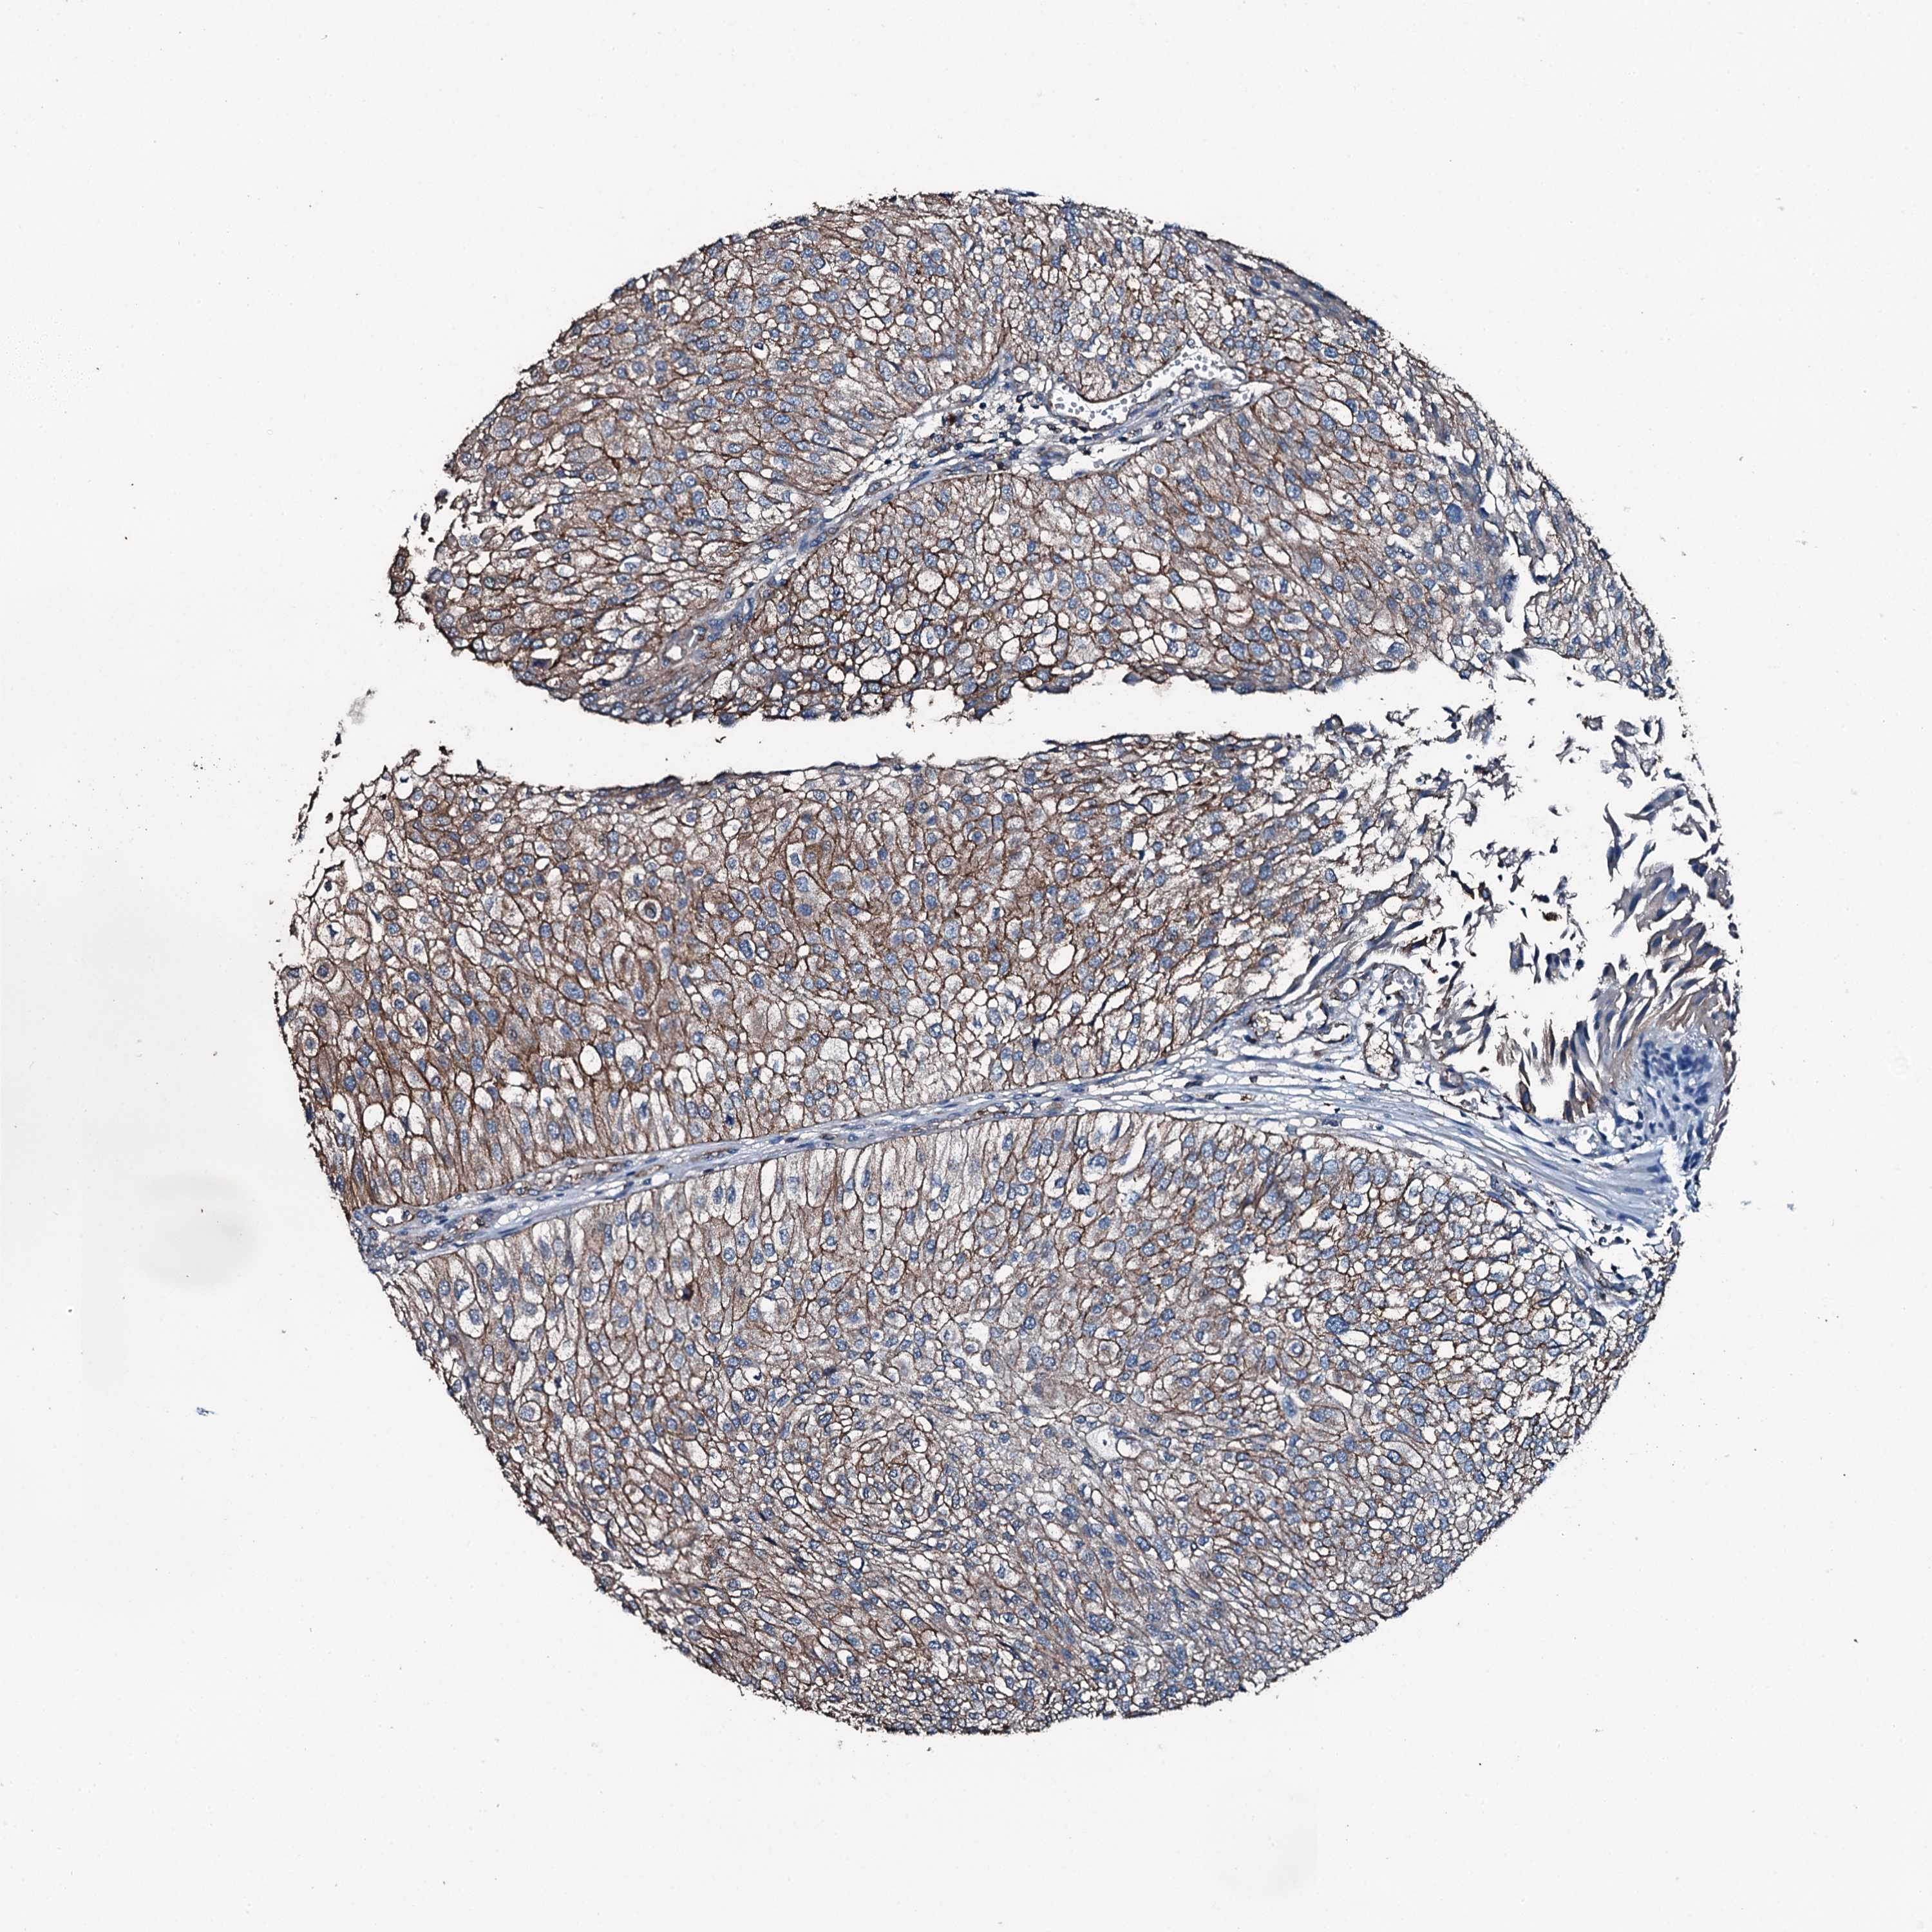

UROTHELIAL CANCER - Protein expressioni

A mouse-over function shows sample information and annotation data. Click on an image to view it in a full screen mode. Samples can be filtered based on level of antibody staining by selecting one or several of the following categories: high, medium, low and not detected. The assay and annotation is described here.

Antibody stainingi

Antibody staining in the annotated cell types in the current human tissue is reported as not detected, low, medium, or high, based on conventional immunohistochemistry profiling in selected tissues. This score is based on the combination of the staining intensity and fraction of stained cells.

Each image is clickable and will lead to virtual microscopy that enables deeper exploration of all samples and also displays staining intensity scores, fraction scores and subcellular localization as well as patient and tissue information for each sample.

Antibody HPA041027

Staining

High

Medium

Low

Not detected

Intensity

Strong

Moderate

Weak

Negative

Quantity

>75%

75%-25%

<25%

None

Location

Nuclear

Cytoplasmic/membranous

Cytoplasmic/membranous,nuclear

Urothelial carcinoma, High grade

Urothelial carcinoma, Low grade